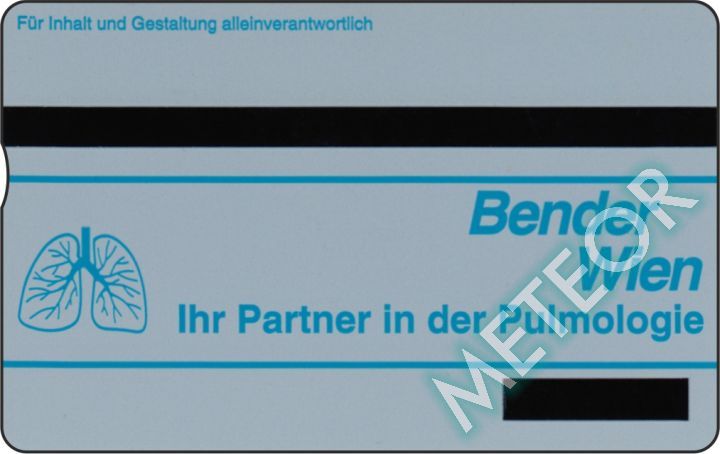

Meteor-Code: TKA P358

ANK-Nummer: P 358

Herausgeber: Telekom Austria

Auflage: 1.000

Seriennummer: 408L 02000 - 02999

Schlagworte: Pharmazie